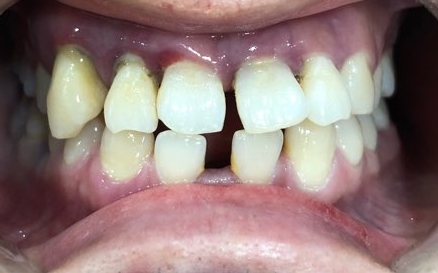

처음오셨을 때 상태이구요

여러 충치치료를 받으셨는데 환자분이 벌어진 앞니가 아무래도 신경이 쓰이셨던 모양이에요.

앞니가 벌어져 있다보니 발음도 많이 새는 상태이구요.

아래 앞니는 일반적인 분들보다 2개가 없는 상태였구요,